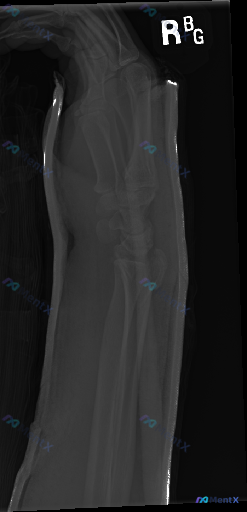

右侧腕关节侧位X光片,这组影像表现最核心的异常是什么?

整理到一份右侧腕关节急性创伤后的侧位X光影像分析资料,先和大家同步一下关键发现:

- 骨骼方面:桡骨远端可见骨折线,累及关节面,骨折远端向背侧移位、背侧成角,掌倾角完全丧失;尺骨茎突基底部也有骨折线。

- 关节方面:桡腕关节对合关系改变,关节面不平整,有碎块;近排腕骨(如月骨)随桡骨向背侧移位,腕骨间排列紊乱;下尺桡关节对合受干扰,有不稳定表现。

- 骨质密度:整体在正常范围,未见明显骨质疏松、溶骨性或成骨性破坏。

- 软组织与其他:骨折周围弥漫性肿胀,密度增高;影像中可见外固定装置(石膏/夹板)的高密度边缘。